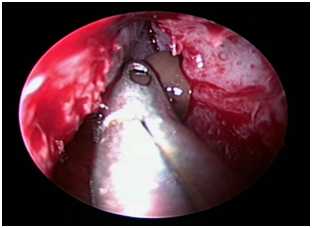

The patient was posted for endoscopic marsupialization of the mucoceles. The mucocele sac from ethmoid sinus was incised and the mucus was drained out (Figure 4 & 5) following which another mucocele sac was identified in the frontal sinus and was drained out (Figure 6 & 7) thus confirming the diagnosis of multiple mucocele introperately.

Figure 4 Intraoperative picture showing right ethmoidal mucocele.

Figure 5 Intraoperative picture taken after draining right ethmoidal mucocele.